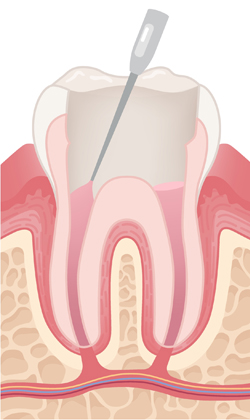

잘 소독된 뿌리관 공간을 영구 재료로 빈틈없이 채워 세균이 다시 침투하지 않도록 봉쇄하는 중요한 단계입니다.

필요 시 치아를 지지할 기둥을 넣고, 접근 통로로 만든 구멍을 충전재로 메워 치아의 구조를 안정적으로 회복시킵니다.